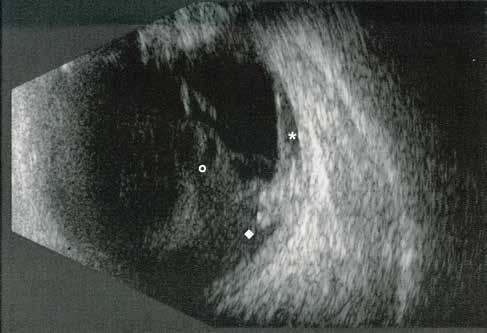

Type 3 MNV refers to the growth of vessels from the retinal circulation toward the outer retina. It is believed that vascular proliferation begins in the deep retinal capillary plexus, with the growth vector extending toward the outer retina. On FA and ICGA, Type 3 MNV appears as a hyperfluorescent intraretinal vascular complex with leakage in the late phases of the examination. Late-phase leakage ion ICGA is a unique feature of MNV lesions. Since these lesions originate from the retinal circulation, they never arise within the foveal avascular zone. Instead, they develop near its edge or at a variable distance from it, typically from the terminal portions of third-order arterioles and venules.5 (Figure 3)

Figure 3. Two examples of Type 3 macular neovascularization. In the first case, Indocyanine green angiography (B) and fluorescein angiography revealing the Type 3 macular neovascularization (arrowhead). Optical coherence tomography (C) showing the detachment of retinal pigment epithelium with the hyperreflective material related to the neovascularization. In the second case, optical coherence tomography (E) showing the intraretinal hyperreflective material related to the neovascularization with intraretinal fluid. Fundus autofluorescence (F) showing abnormalities of retinal pigment epithelium. Optical coherence tomography angiography (G) showing the neovascular lesion.